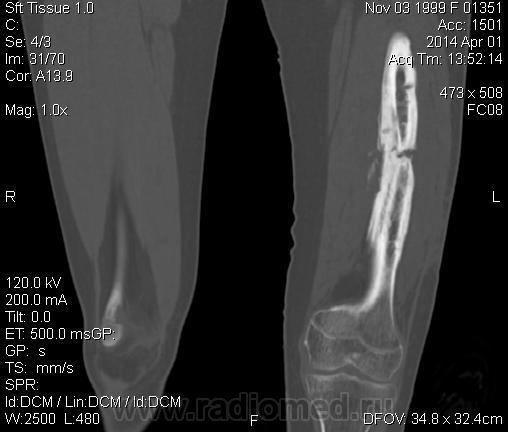

Молодая дама (14 лет) с переломом срдней трети диафиза левого бедра в анамнезе (декабрь 2012 г). Ломала ногу несколько раз в этом месте. Сейчас состояние после МОС. Как следует понимать изменения в кости, формируется ли ложный сустав?

Похоже ложный сустав сформировался. Но при нём обычно большие напластования костной мозоли, здесь их нет. В таких случаях смотрю при скопии подвижность.

Ох, не хочется думать о ложном суставе в 14 лет... По срокам под ложный сустав подходит, он характеризуется замыканием костномозгового канала с формированием подобий суставных поверхностей. У нее же есть хиленькая периостальная костная мозоль по задней поверхности бедра удерживающая отломки в правильном положении. Я склонна думать, что это скорее застарелый перелом (оно же замедленная консолидация). Здесь очень важно посмотреть предыдущие снимки (поиск рефрактуры, либо отсутствия полной консолидации).

Настоящего, родного ложного сустава пока нет, хотя костномозговой канал дистального отломка уже закрыт - образовалась склерозированная замыкательная пластина. Варусная деформация почти в 165 градусов... Я бы заключилась неполной консолидацией и варусной деформацией, прогностически формирование ложного сустава очень вероятно.